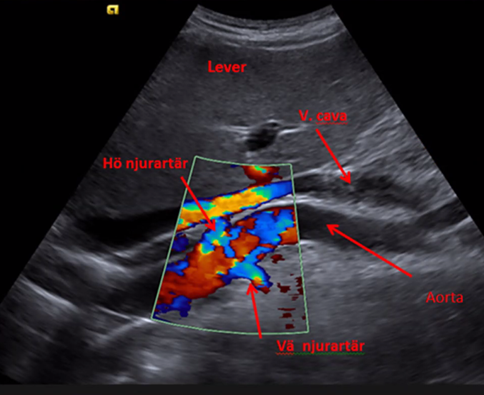

Underlättas genom doppler med färgsättning

Vad kan vi se här?

Plaque yta/ruptur (se krater i undre bilden), färgdopplern sätts på och vi kan se att blod svirar runt